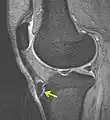

IRM d'un Osgood-Schlatter- Radiographie d'un Osgood-Schlatter

Une radiographie n'est pas nécessaire notamment lorsque le tableau clinique est évocateur et que les douleurs sont bilatérales. Elle peut être utile pour éliminer une autre pathologie si les douleurs sont unilatérales, atypiques ou rebelles au traitement. Initialement on retrouve un soulèvement de la tubérosité tibiale antérieure avec élargissement de son cartilage de croissance ; dans les stades plus évolués, la TTA est fragmentée et on peut voir parfois des calcifications dans le ligament rotulien[2].